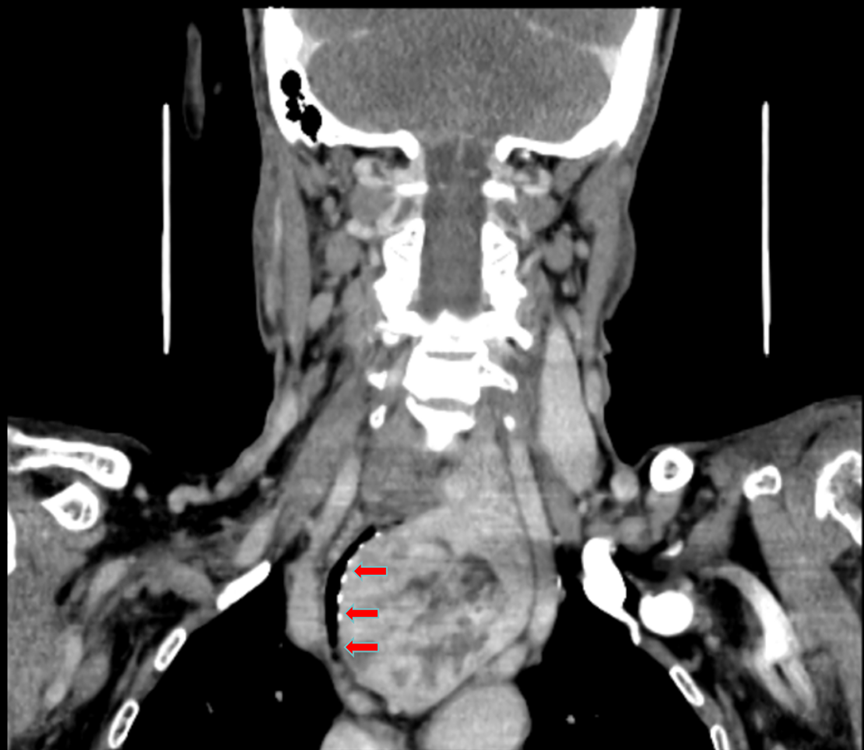

患者张大叔(化名)持续腹痛一个多月,进食后疼痛、恶心与食欲不振,令直肠癌术后的他更加虚弱。在其他医院胃镜检查提示胃溃疡、巨大胃结石(大小约10厘米*5厘米)及慢性胃炎。更棘手的是,初次尝试内镜碎石因结石“质地坚硬,无法切割”而告失败。

为了早日取出胃里的大“石头”,张大叔就诊于康复大学青岛中心医院消化内二科。科室主任贺延新通过问诊、查看检查报告,判断这颗持续摩擦胃壁的褐色“巨石”,是导致患者疼痛与溃疡迁延不愈的元凶。然而,“石头”不仅巨大,还因形成时间长导致质地坚硬。面对患者复杂的身体状况与较高的治疗风险,贺延新带领团队没有贸然强攻,而是制定了“先稳后治、分阶段碎石”的“三步走”个体化方案。